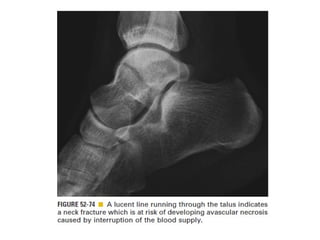

Skeletal trauma was presented by Dr Laith Fadhel with reference to Grainger's Diagnostic Radiology textbook. The presentation covered skeletal trauma as assessed through diagnostic radiology techniques. Key findings and treatments for skeletal injuries were likely discussed.